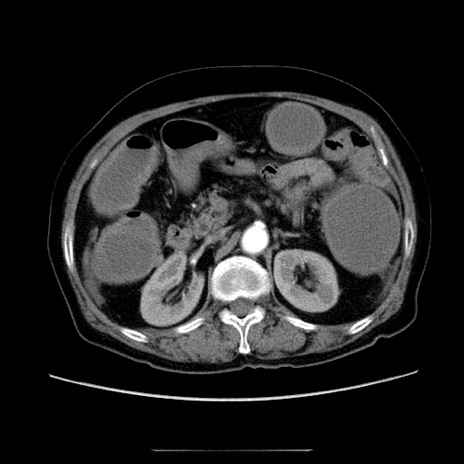

冠状断像

【症例】70歳代女性

【主訴】お腹が張る

【現病歴】1週間くらい前から腹部膨満の自覚あり。昨日夜から増悪したため、本日救急外来受診。

【身体所見】意識清明、BT 36.5℃、BP 165/106mmHg、HR 80bpm、SpO2 98%、腹部:膨満、軟、自発痛・圧痛なし、触診にて不快感あり、腸蠕動音:減弱

【データ】WBC 12600、CRP 1.04